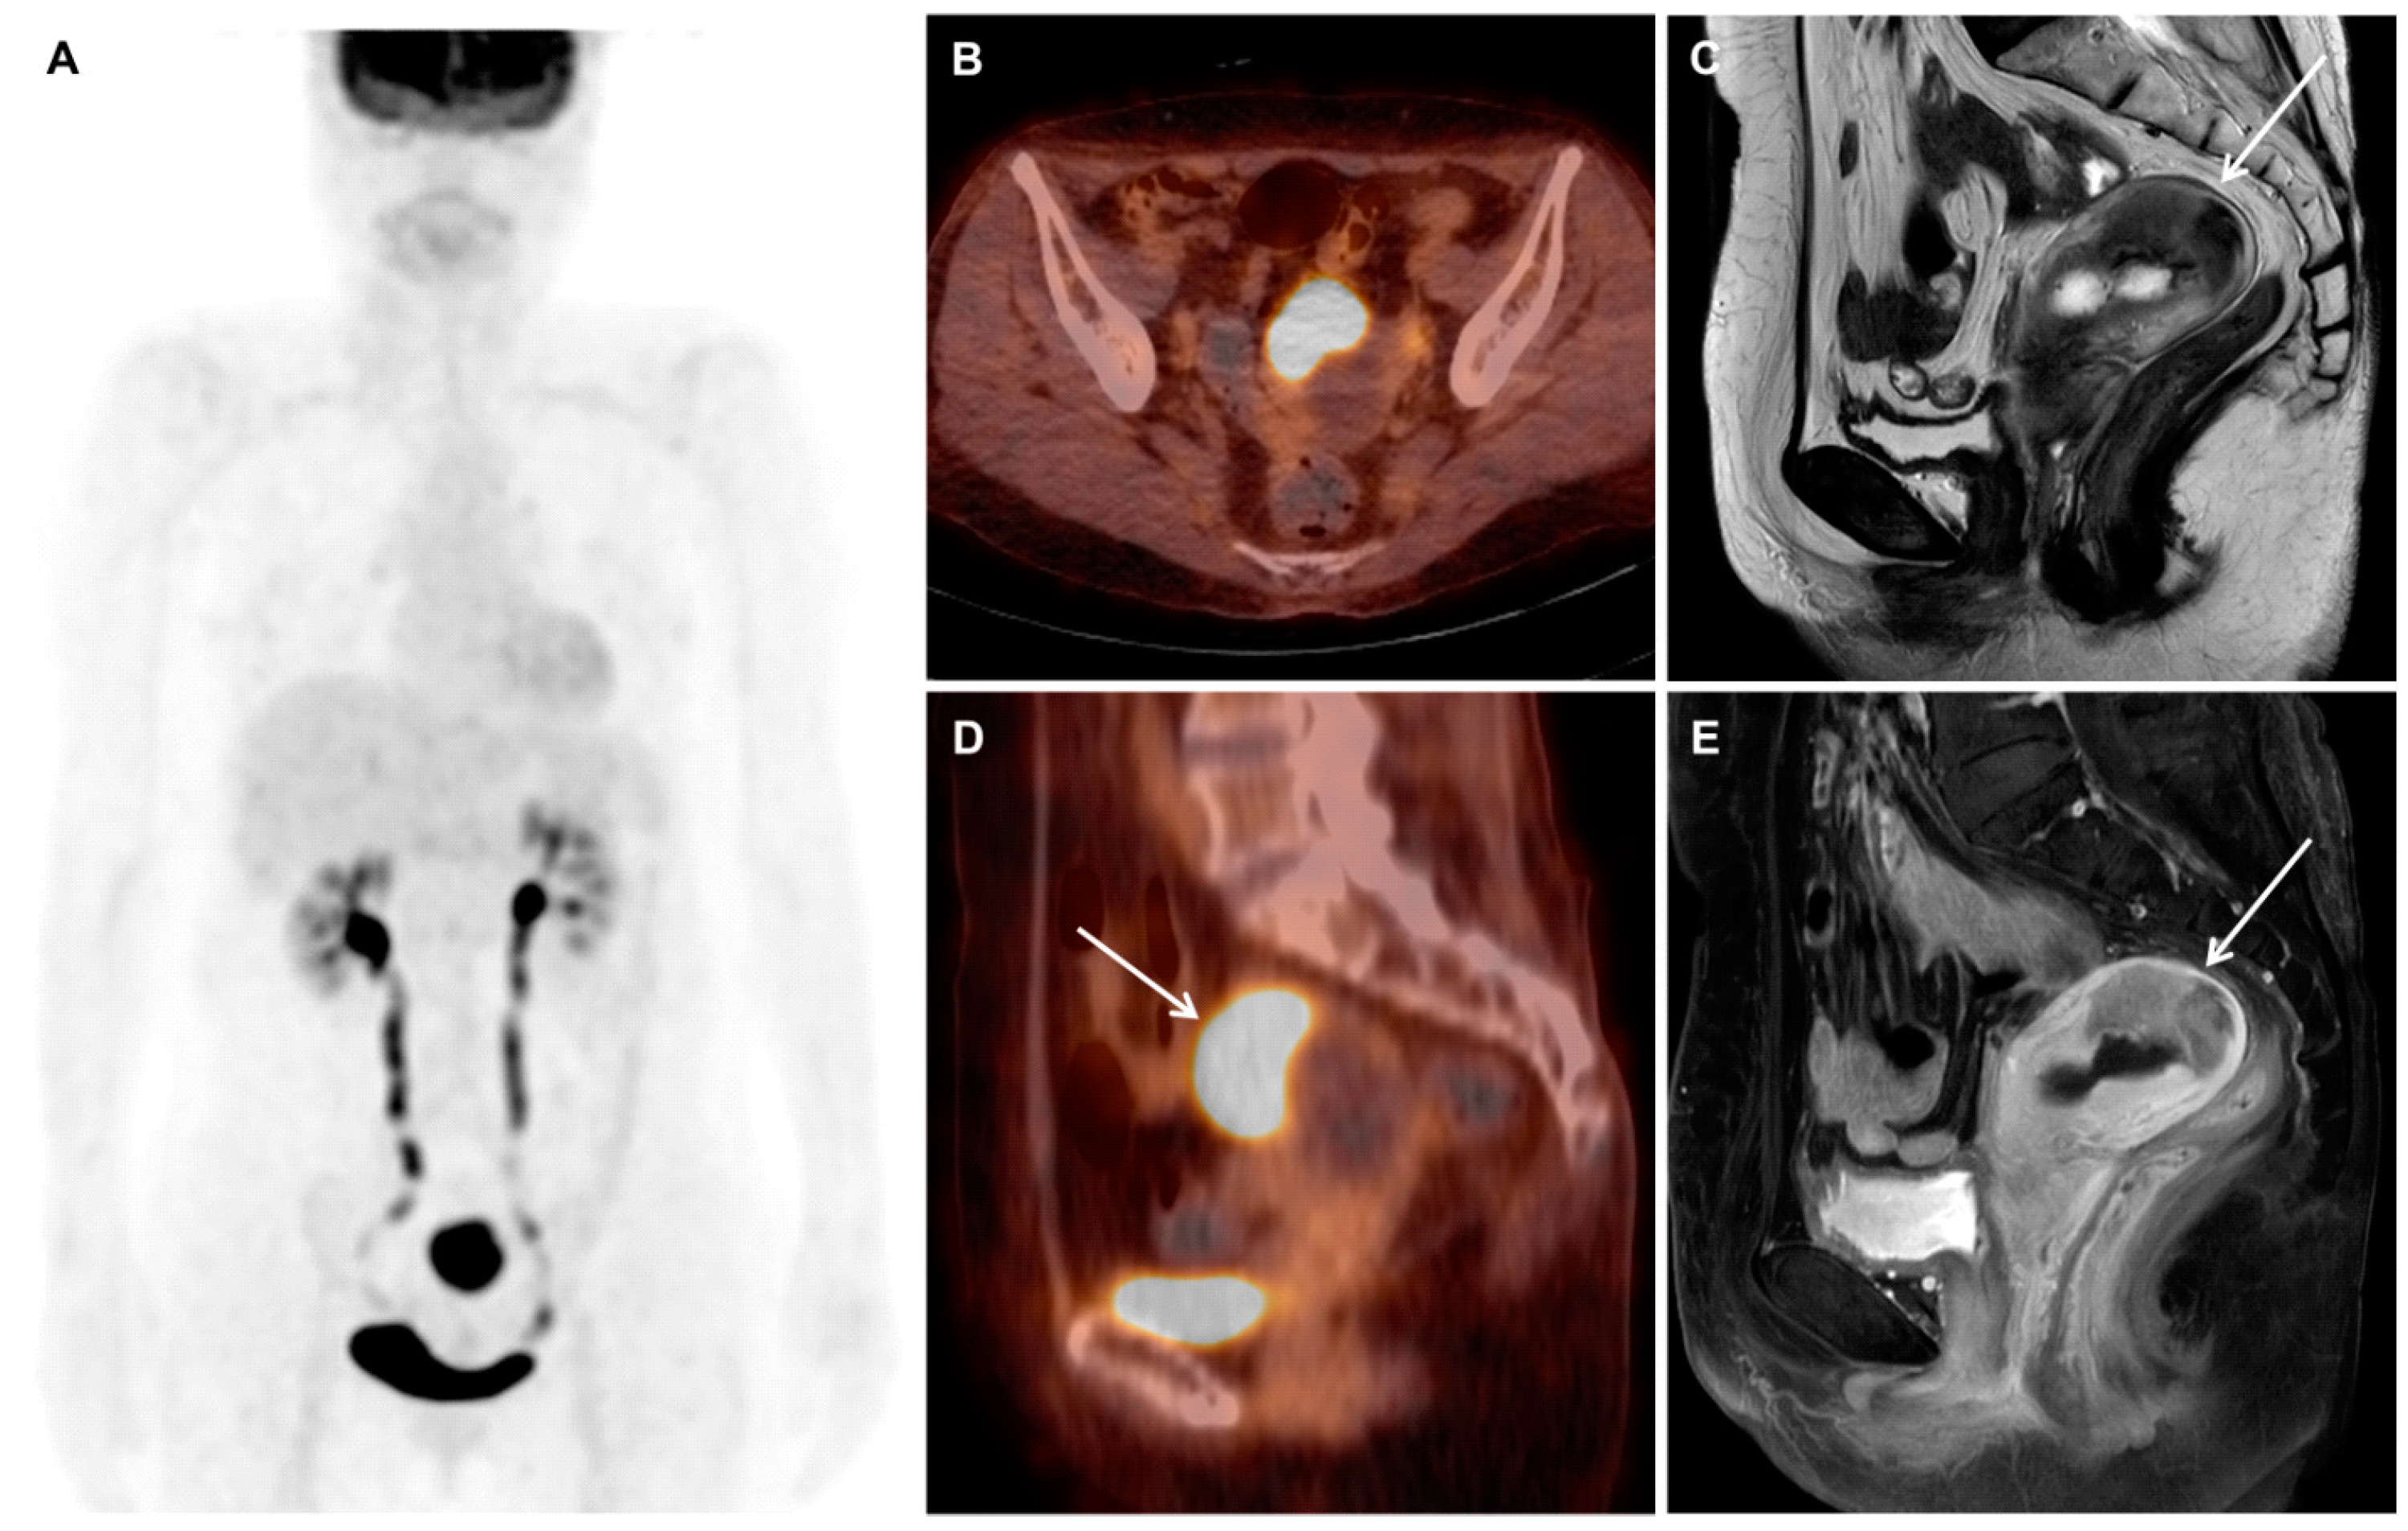

Mesonephric Adenocarcinoma of the Uterine Fundus Exhibiting High 18F-FDG Uptake